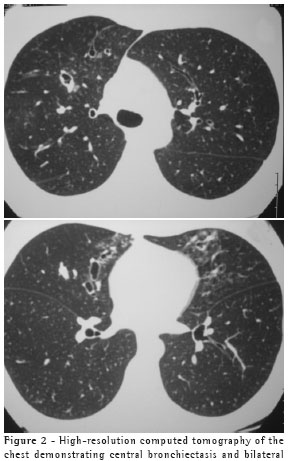

were bilateral and diffuse. Additional examinations showed the following: normal spirometry results, positivity for A. fumigatus in immediate cutaneous reaction allergy testing (skin prick test); eosinophilia (13%) in the blood workup; total serum IgE levels higher than 1000 ng/ml; and radioallergosorbent test (RAST) class 3 in the determination of specific IgE for A. fumigatus. On the chest X-ray, glove-finger shadows were observed in the right superior third (Figure 1). The high-resolution computed tomography scan revealed central bronchiectasis (Figure 2).

In various studies, the changes observed on the chest X-rays of patients with ABPA have been described as extensive consolidations and alveolar infiltrate, predominantly occurring in the superior lobes, together with mucoid impaction in the central bronchus. The findings known as the glove-finger shadow and the toothpaste shadow are transitory images of mucoid impaction, which can disappear with cough or after corticosteroid administration.(7-9) On the chest X-ray, opaque shadows in glove-finger form were observed in the upper third of the right hemithorax (Figure 1). On the high-resolution computed tomography scan, there were signs of central bronchiectasis (Figure 2). According to the literature, glove-finger shadows are suggestive of ABPA,(10) reflecting inflammation, thickening, and dilation of the bronchial tree caused by the mucoid impaction in the airways.(11) In order to , It has been suggested that high-resolution computed tomography is the best diagnostic technique for detecting central bronchiectasis, for which chest X-ray is neither sensitive nor specific.(4)